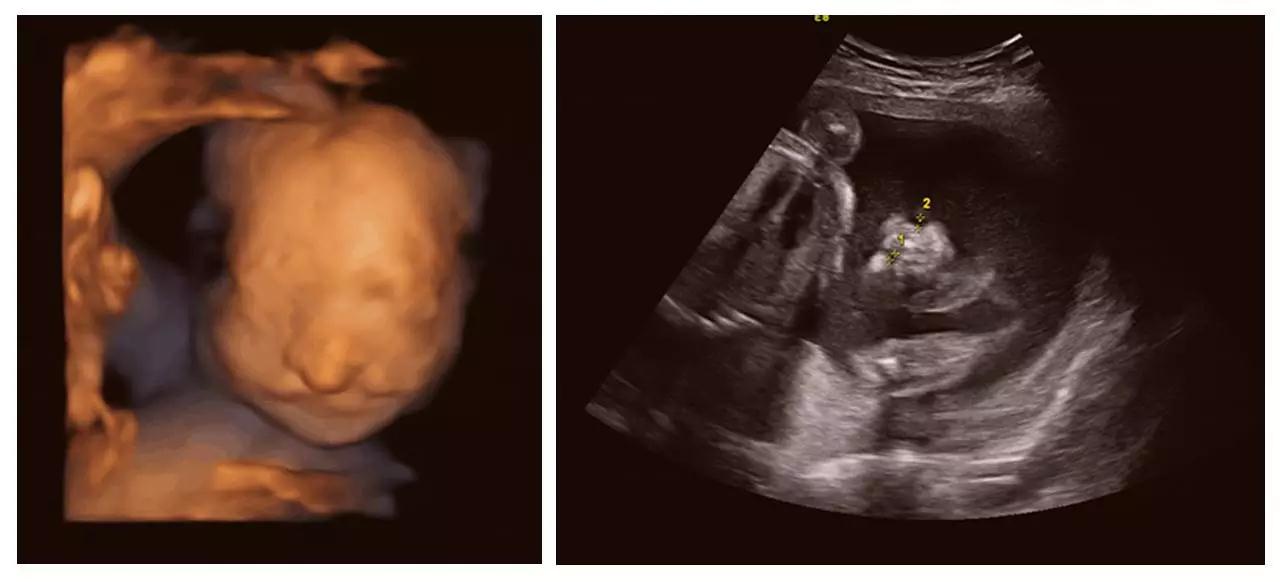

艾玛妇产成功筛查胎儿畸形的案例(部分)——

(右手多指畸形)

(单侧唇裂)

(双侧唇裂)